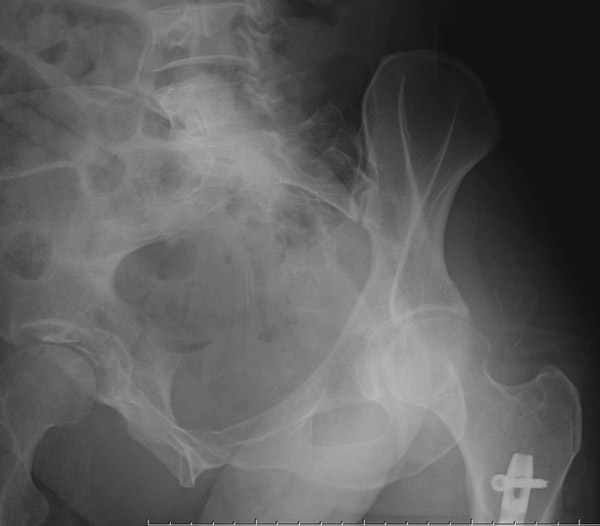

Перелом вертлужной впадины отличается от “переломов таза” не только исследованием, но также тактикой. По классификации Летурнеля расположение линии перелома характерно для поперечного перелома вертлужной впадины, но наличие шурупов в заднем крае (второй снимок) и вывих бедра подтверждают, что здесь сочетание заднего края с поперечным переломом.

Через задний доступ смогли сделать частичную репозицию, а здесь напрашивался двойной доступ спереди и сзади. Репозиция в положении на боку затруднительна, и вытяжение за перекладину над операционным столом облегчило бы репозицию.

Здесь пара случаев, где обычный поперечный перелом зафиксирован задним доступом и второй поперечный перелом в сочетании задней стенки, где на КТ слева в шейке обнаружен перелом без смещения, который зафиксирован профилактически.

В большинстве вывих происходит при переломах задней стенки, а без хорошей фиксации головку невозможно удержать! Про осложнения можно говорить еще, но навряд ли Вам интересно отдуваться за чужой грех. И если Вы не из WikiLeak, который сливает чужие осложнения, а ваше желание помочь искреннее, тогда надо организовать необходимые снимки и исследовании. Возможно, не все потеряно и какой-нибудь ближайщий центр протянет руки помощи....